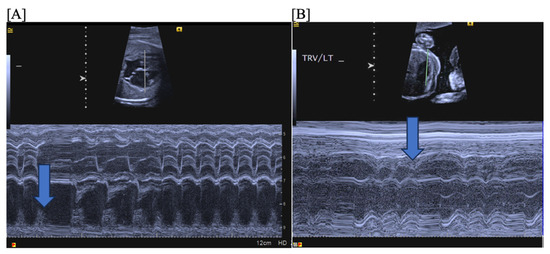

- Short VA SVT (Figure 3 and Figure 4) demonstrates a ventricular–atrial (VA) interval that is less than half of the ventricular–ventricular (VV) interval (VA:AV ratio < 1) and a sudden onset and termination of tachycardia; tachycardia usually terminates with a non-conducted atrial contraction. Short VA SVT includes AVRT (also known as orthodromic reciprocating tachycardia, ORT) and atrioventricular nodal reentrant tachycardia (AVNRT). Short VA SVT typically presents after 18 weeks of gestation.

- Long VA SVT (Figure 4) demonstrates a VA interval that is more than half of the VV interval (VA:AV ratio > 1). Long VA SVT includes EAT and PJRT. A distinguishing feature of EAT is tachycardia termination with ventricular contraction. Long VA SVT may occur as early as 12 weeks of gestation. Because long VA tachycardias have slower rates, they are less likely to cause hydrops.